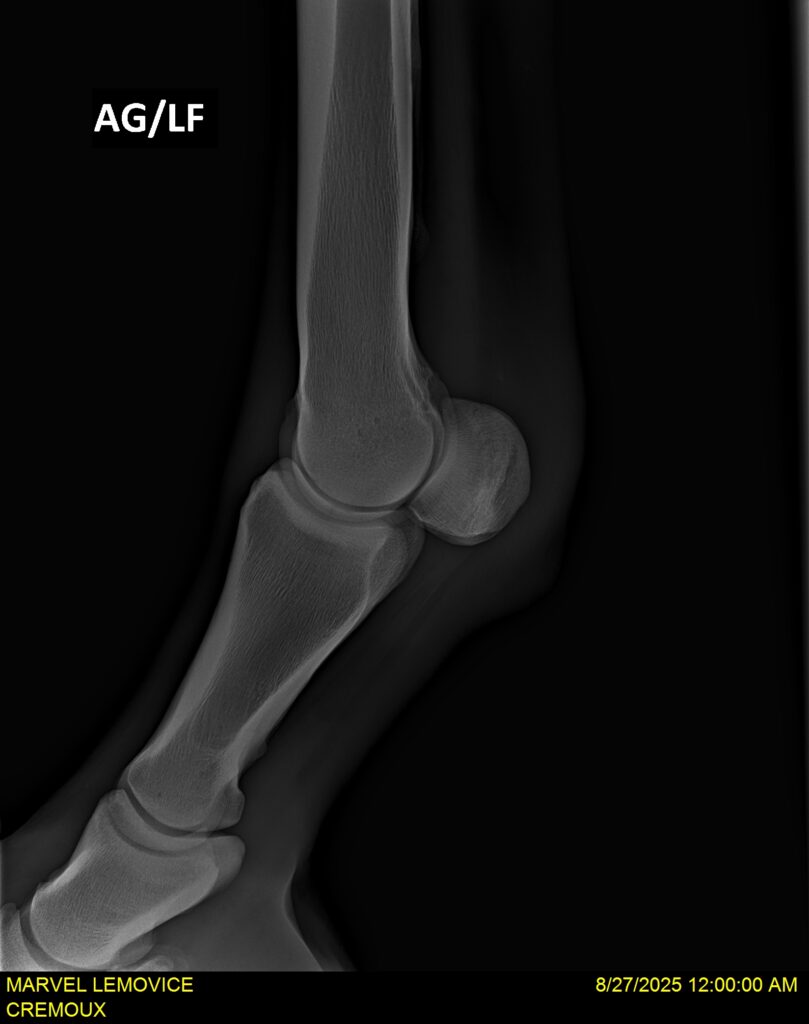

MARVEL LEMOVICE, hongre, Selle Français prend 4 ans en 2026. POPSTAR LOZONAIS x ROSIRE sur une excellente souche maternelle de l’élevage PLATIERE. Débourré aux trois allures et mise en route à l’obstacle. Super modèle avec du cadre et de la force, cheval respectueux avec des moyens. Très agréable au quotidien. Transport OK, maréchalerie OK, santé RAS, Bilan 20 clichés radios + clinique OK.

RADIOS ET CLINIQUE